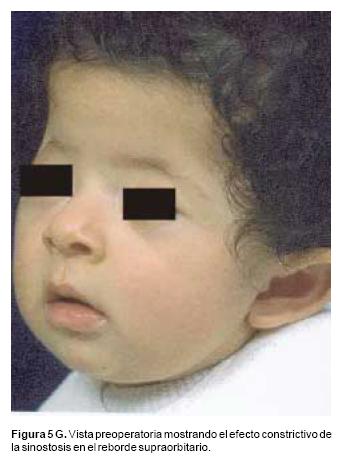

También los controles radiológicos durante el proceso de distracción mostraron que no se produjo la creación de espacios muertos intracraneanos durante los avances. En todos los pacientes con sinostosis bicoronal el avance frontoorbitario produjo excelentes resultados estéticos dando una nueva forma a la región frontal y proyectando mejor el reborde supraorbitario. En los niños con enfermedad de Crouzon y síndrome de Apert, se corrigió en forma muy satisfactoria el exorbitismo al resolver las graves exposiciones corneales (Figuras 5 A, B, C, D, E, F, G, H), en los que se utilizó el avance simultáneo del tercio medio, este cambio óseo corrigió muy satisfactoriamente la retrusión del mismo, ampliando la vía aérea y resolviendo en muchos casos grandes problemas ventilatorios durante el sueño (Figuras 6 A, B, C, D, E, F). Los pacientes con plagiocefalia corrigieron significativamente la deformidad frontoorbitaria y los tejidos blandos suprayacentes se adaptaron a la nueva estructura ósea. La clásica órbita de arlequín de estos niños producida por la sinostosis del frontal con el esfenoides, inmediatamente se ve corregida en su forma y su configuración se hace muy similar con la órbita contralateral (Figura 7)(Fig. 7a, 7b, 7c, 7d, 7e, 7f, 7g) (Cuadro II).

a Los que avanzan el tercio medio de la cara, que generalmente utilizan un vector distraccional oblicuo, de arriba hacia abajo (Figura 5). El distractor se apoya en la unión de la órbita y el hueso malar, o en la cara posterior del malar. Esta dirección de distracción avanza el maxilar, los malares y la mitad inferior de las órbitas recreando la curva de crecimiento, que el tercio medio de la cara normalmente realiza durante el desarrollo y evita la producción de alteraciones oclusales como las graves mordidas abiertas anteriores u otras, b Los que avanzan el hueso frontal y el reborde supraorbitario, son un par de distractores que tienen un vector horizontal. Especialmente en niños con edades entre los 9 y los 14 meses durante el avance, es importante evitar la fractura de la unión frontoorbitaria, debido a que ésta es una unión ósea muy lábil en estas edades y la fuerza producida por estos distractores durante su activación puede producir fácilmente esta fractura.